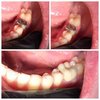

Врач стоматолог терапевт,ортопед,хирург

Лечение,удаление,протезирование,имплантация

Стоматолог : Терапевт,Ортопед ;Хирург

Терапевт,Ортопед,Хирург-имплантолог